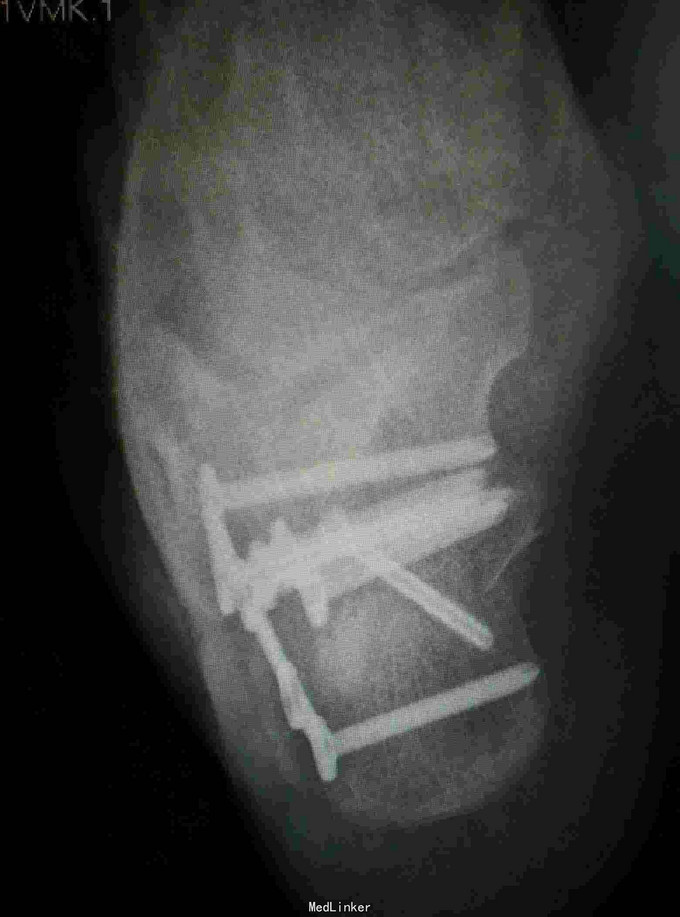

诊断:右跟骨粉碎性骨折 治疗:骨折切开复位内固定

随访:3月内避免患肢负重,3月后视复查情况决定是否负重,行功能锻炼。 讨论:跟骨骨折有部分患者远期效果并不特别好,尤其是骨折涉及关节面,术中应尽量复位。还有就是需要视软组织情况选择合适的固定方式。